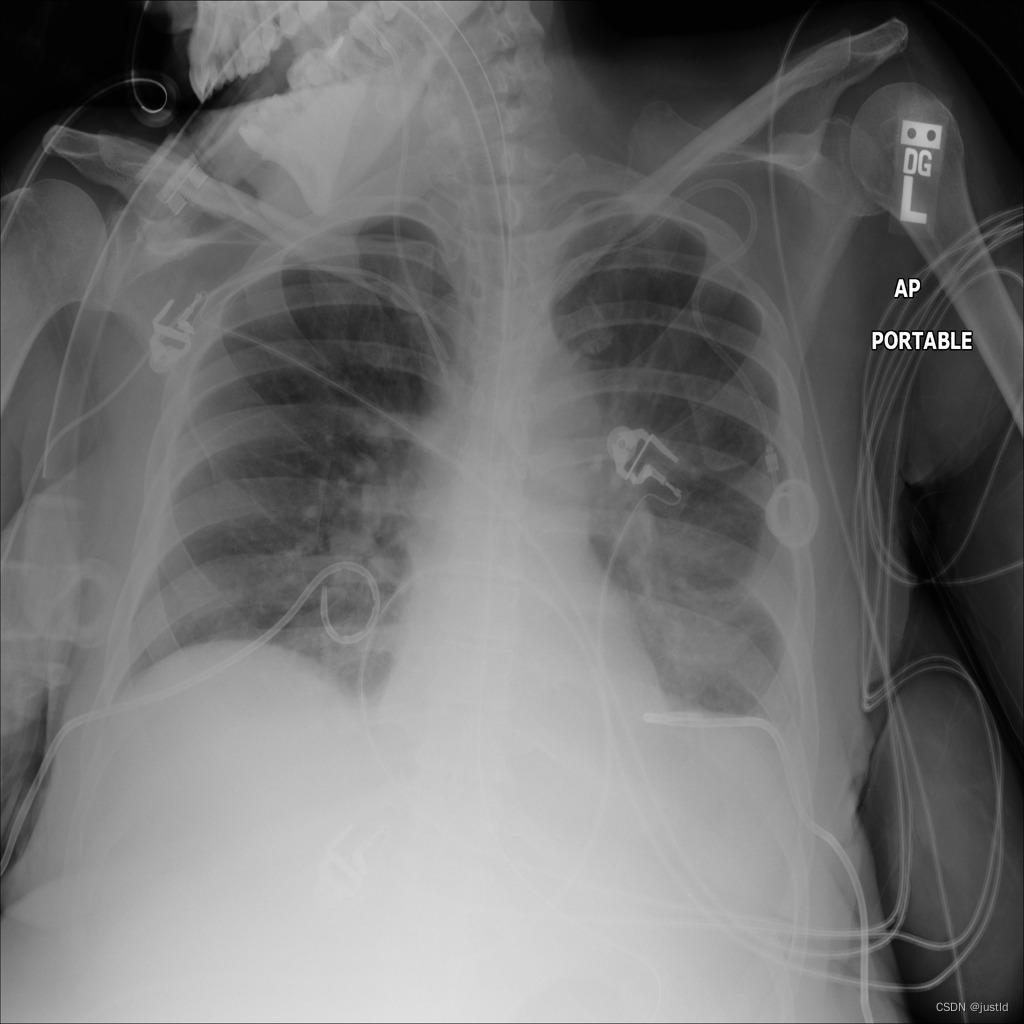

检测结果如下图:

该数据集包含5950个训练数据,662个测试数据,数据如下图: